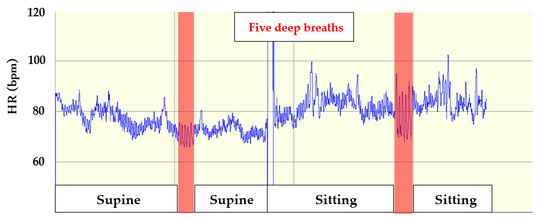

Mind-Body Connection Test

この患者のMind-Body Connection Test

X線画像に異状がなく関節の可動域が正常でない場合は、軟部組織の機能不全が起きていると考えられます。しかし、MBCTにより、心臓交感神経の過緊張が認められるため、心臓副交感神経の機能亢進、心臓交感神経の機能抑制を視野に入れての施術が必要である。また、デスクワークと聞き、パソコン画面の場所など、仕事環境の問診から、日常生活の聞き取りから改善の手法をお伝えしている。